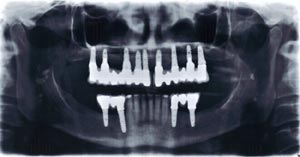

Protesi fissa completamente ancorato ad impianti in arcata superiori e riabilitazione parziale su impianti nei settori posteriori ed anteriori

Radiografia panoramica